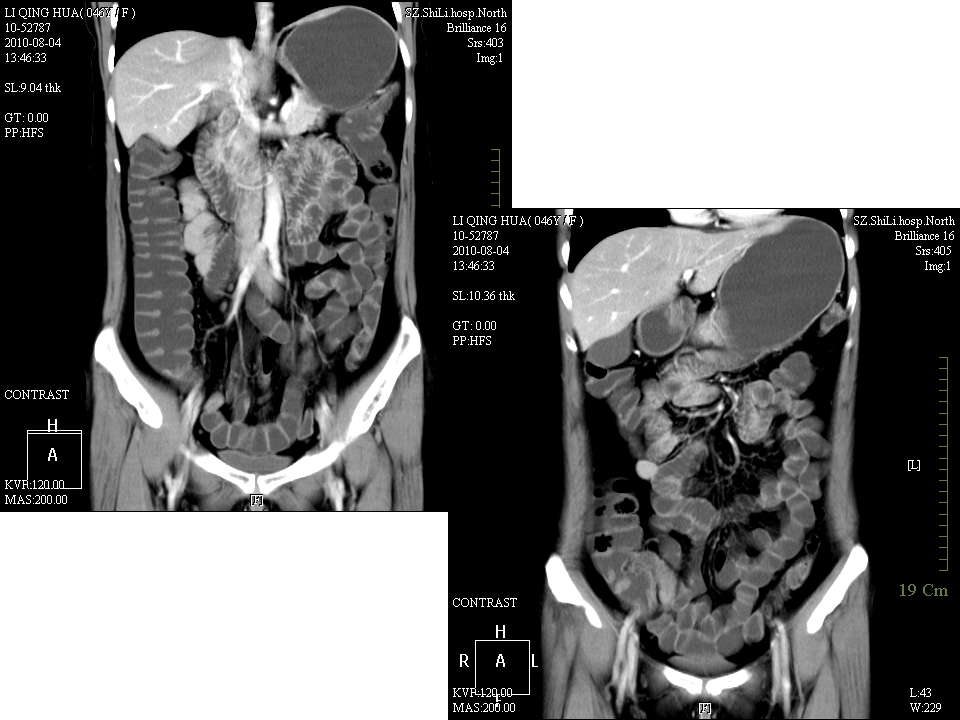

克罗恩病的MDCT诊断价值.ppt